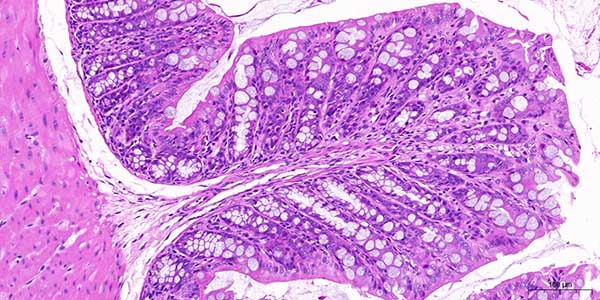

病理染色全景数字扫描技术具有多方面显著优势,以下是其主要好处:

3. 高分辨率与精准成像 清晰细节:支持高倍率(如40x-1000x)光学放大,图像分辨率可达0.2微米/像素,清晰呈现细胞形态、染色特征及微小病灶,辅助精准诊断。 色彩还原:采用多光谱成像和色彩校正技术,确保染色图像真实还原,减少人为误差。